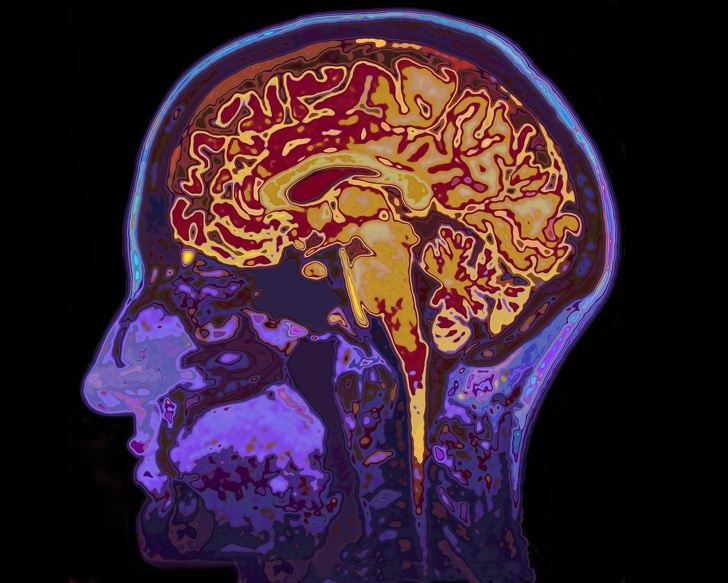

Ένα από τα πιο συνηθισμένα συμπτώματα είναι μια κατάσταση που προκαλεί μπερδεμένη ή αργή ομιλία. Αυτό συμβαίνει επειδή οι περιοχές του εγκεφάλου που ελέγχουν τους μύες για ομιλία έχουν πάθει βλάβη.

Οι ασθενείς μπορεί να ξέρουν ακριβώς τι θέλουν να πουν, αλλά είναι δύσκολο γι ‘αυτούς να το διατυπώσουν.